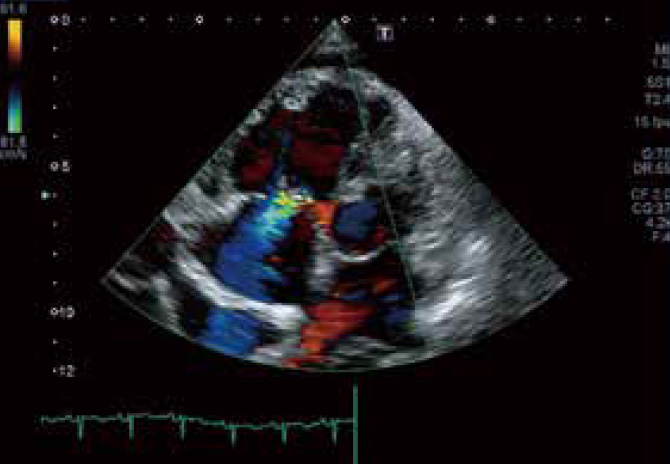

実践に活きる 臨床心エコー図法 | 伊藤 浩, 渡辺 弘之 |本 | 通販 | Amazon。基本をおさえる心エコー 改訂版〜撮りかた、診かた、考えかた - 羊土社。循環器 | 株式会社文光堂。。「実践に活きる 臨床心エコー図法」伊藤 浩 / 渡辺 弘之定価: ¥ 25000+税#伊藤浩 #伊藤_浩 #渡辺弘之 #渡辺_弘之 #本 #自然/医療・薬学・健康数ページ書き込みがありますが、問題無く読めます。m3電子書籍 | レジデントのための 心エコー教室。レビュー